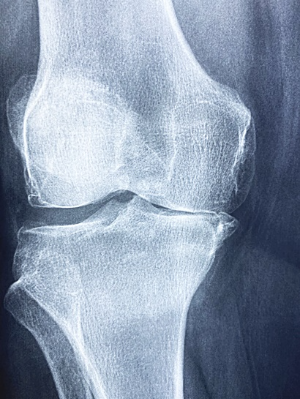

무릎이 아픈 경우, 일상생활에 큰 어려움을 겪게 됩니다. 다양한 원인들이 이런 무릎 통증을 초래하는데, 그중에서도 특히 무릎을 과도하게 사용하여 관절에 부담을 주는 경우입니다. 이는 연골이 찢어지거나 닳아서 발생하는 것인데, 신체를 적절히 활용하는 것은 근육을 강화하고 관절을 안정화시키지만, 과도한 활동이나 잘못된 자세로 인해 오랜 시간 동안 무릎에 부담을 주면 문제가 생길 수 있습니다. 따라서 일상생활에서는 이를 주의하며 살아가야 합니다.

무릎 통증은 일반적으로 자주 발생하는 증상으로, 달리기나 앉기 등의 특별히 행동에 국한되지 않고, 걷기나 서기와 같은 기본적인 활동에서도 흔히 발생합니다. 이는 삶의 질을 크게 저해하게 됩니다.

무릎 통증의 원인은 발생하는 부위에 따라 다르게 나뉘고, 이에 따라 치료법도 달라집니다. 통증의 부위에 따라 앞쪽, 안쪽, 뒤쪽 등으로 구분될 수 있습니다. 그렇기에 이번에는 무릎 통증이 발생하는 다양한 원인에 대해 알아보도록 하겠습니다.